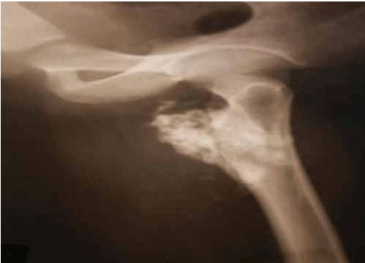

এখানে আমরা প্রক্সিমাল ফেমোরাল অস্টিওকন্ড্রোমার কারণে বাম নিতম্ব এবং উরুতে ব্যথা সহ একজন 28 বছর বয়সী পুরুষ উপস্থিত প্রতিবেদন করি। রেডিওগ্রাফ দেখায় ফুলকপির মতো ভর বাম প্রক্সিমাল ফিমার থেকে উদ্ভূত। বাম উরুর 3D CT স্ক্যান বিভাজনের কাছাকাছি ফেমোরাল জাহাজের সংকোচন পূর্ববর্তী স্থানচ্যুতি দেখায়। এই রোগীকে অস্ত্রোপচারের এন-ব্লক রিসেকশনের মাধ্যমে চিকিত্সা করা হয়েছিল এবং হিস্টোপ্যাথলজি অস্টিওকন্ড্রোমার ডায়াগনস্টিক ছিল।

অস্টিওকন্ড্রোমা বাম ফিমারের সাবট্রোচ্যান্টেরিক অঞ্চলের অ্যান্টেরো-মিডিয়াল দিকের উৎপত্তি যেখানে একটি বৃহৎ কার্টিলাজিনাস ক্যাপ সহ কম ট্রোক্যান্টারকে বিচ্ছিন্ন করে বিভাজনের কাছাকাছি ফেমোরাল জাহাজের সংকোচন পূর্ববর্তী স্থানচ্যুতি ঘটায়।

এক্স-রে করার আগে

প্রিওপ এক্স-রে